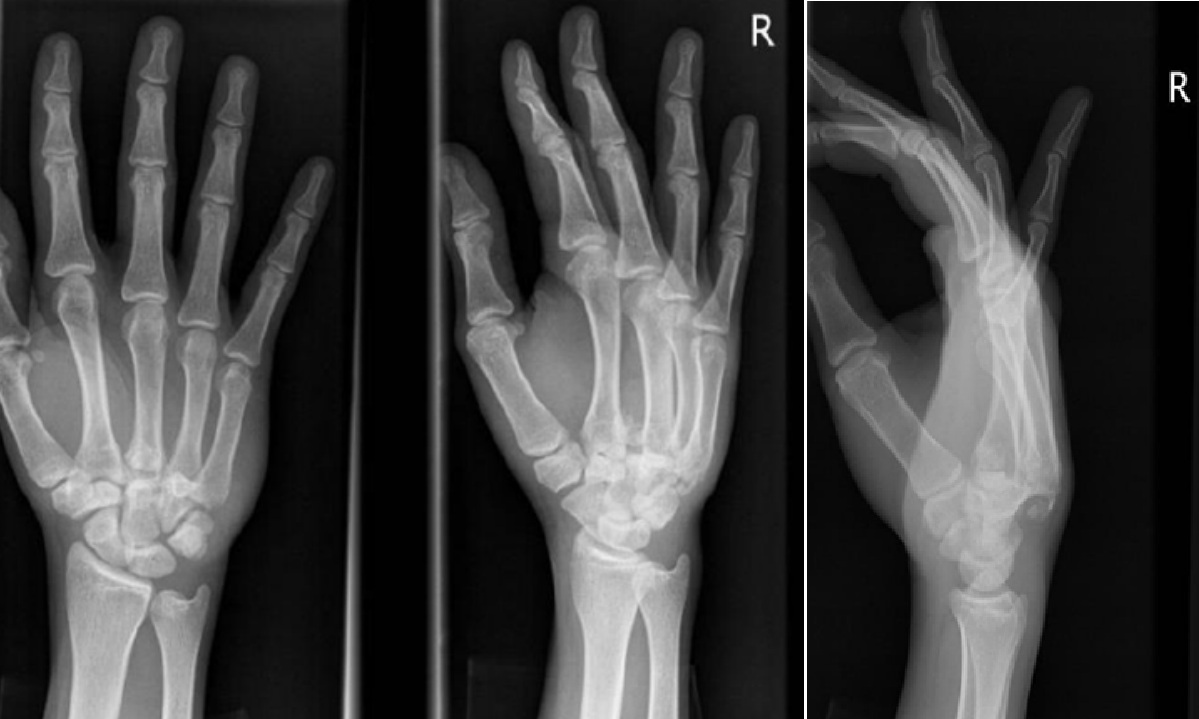

Hand injury

A 20-year-old man presents with a painful right hand after a night out. He cannot recall the mechanism of injury. …